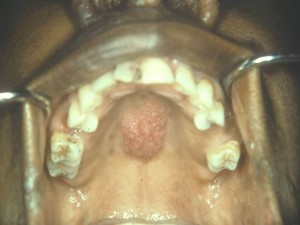

Клиническая картина. В толще слизистой оболочки щек, языка, неба, десен появляются одиночные или множественные узлы. Очаги поражения возвышаются над поверхностью слизистой оболочки. При распаде патологических узлов образуются язвы с папуломатозными разрастаниями и хроническим течением.